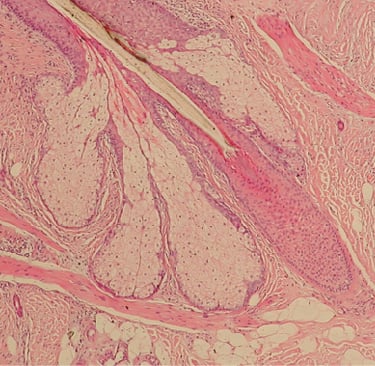

Fizyolojik Mekanizma: Çinko, saç folikül çevresindeki sebaceous bez aktivitesini düzenler. Yeterli çinko, saçlı deride inflamasyonu ve aşırı sebumu azaltarak folikül sağlığını korur.